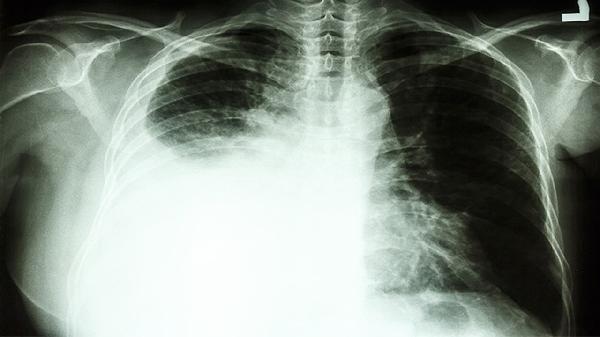

乳癌二期患者需坚持定期复查,包括乳腺超声、乳腺X线检查、肿瘤标志物检测等,以便及时发现复发迹象。若发现异常,需尽早干预,采取进一步治疗措施。复查频率和项目应根据个体情况,由医生制定个性化方案。